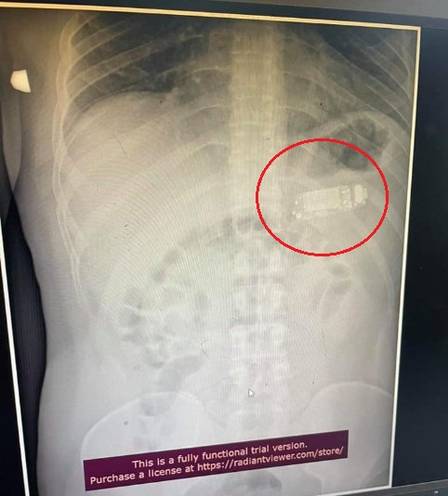

Um homem de 33 anos foi submetido a um procedimento de emergência após engolir um celular Nokia, modelo 3310, popular no início dos anos 2000. Médicos num hospital em Pristina (Kosovo) tiveram que sedar o paciente, não identificado, depois que o telefone se alojara no seu estômago.

O aparelho era muito grande para "ser digerido" e colocava a vida do paciente em perigo, pois o ácido corrosivo da bateria poderia vazar. Skender Teljaku, que liderou a equipe de médicos, postou registros do caso no Facebook, incluindo imagens de raio-x e de endoscopia, quando o aparelho ainda estava no estômago do paciente. Os médicos conseguiram remover o corpo estranho sem cortar o estômago, retirando-o em três partes com ajuda da endoscopia.

Foto: Reprodução / Facebook